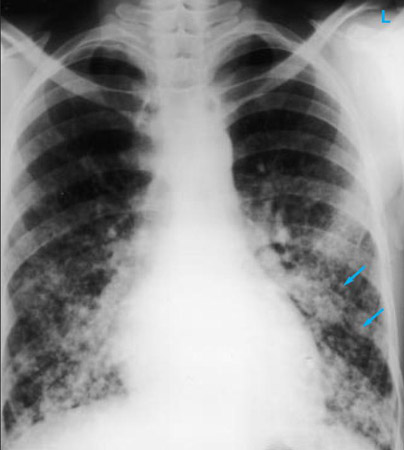

Chest x-ray showing pulmonary tuberculosis with cavitation

From the personal collection of Dr M. Narita, Department of Pulmonary and Critical Care Medicine, University of Washington